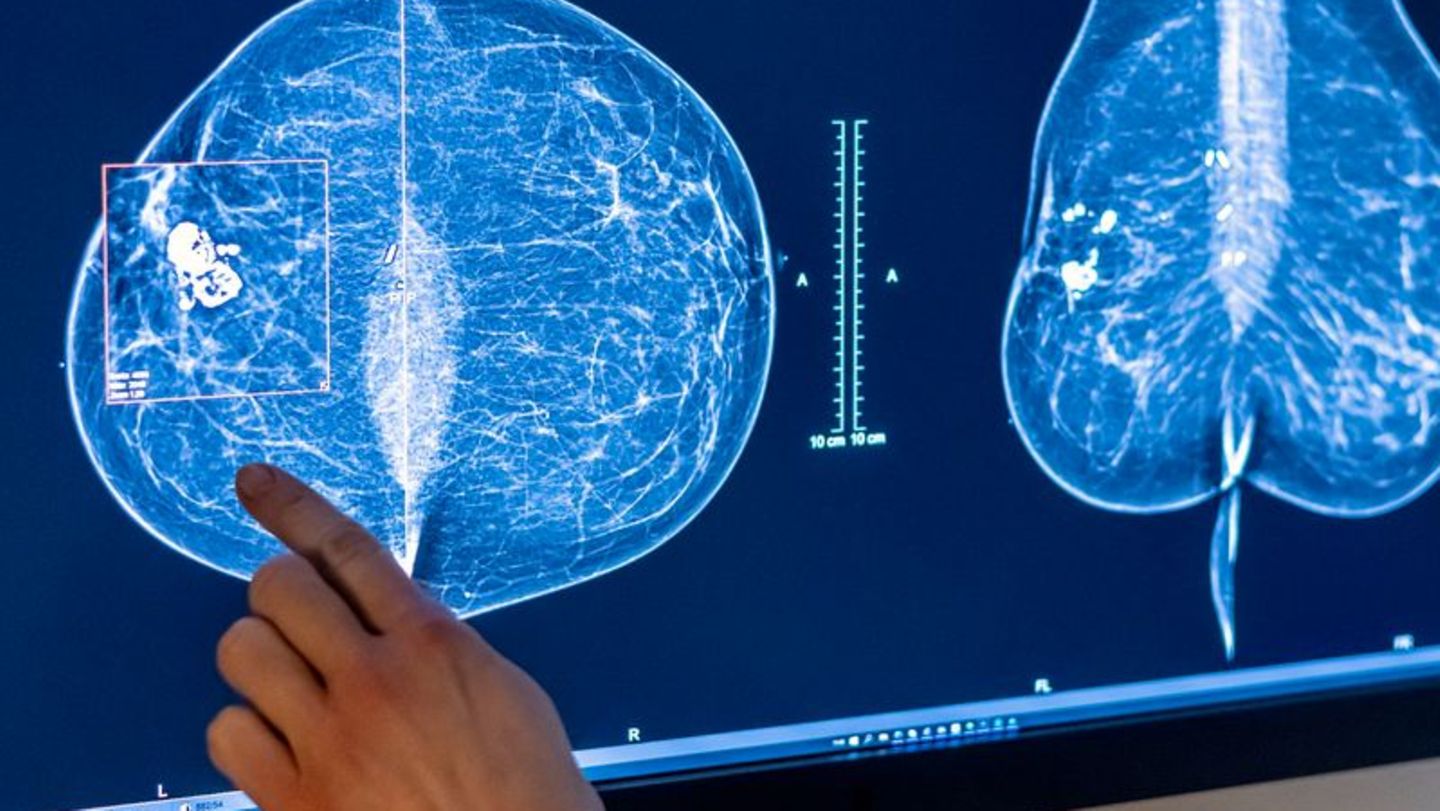

Mammografie in einer Klinik in Berlin. Frauen sind nicht nur von Brustkrebs betroffen, sondern häufig auch von Gebärmutter-, Lun

Mammografie in einer Klinik in Berlin. Frauen sind nicht nur von Brustkrebs betroffen, sondern häufig auch von Gebärmutter-, Lungen- und Darmkrebs.

© Hannibal Hanschke/dpa